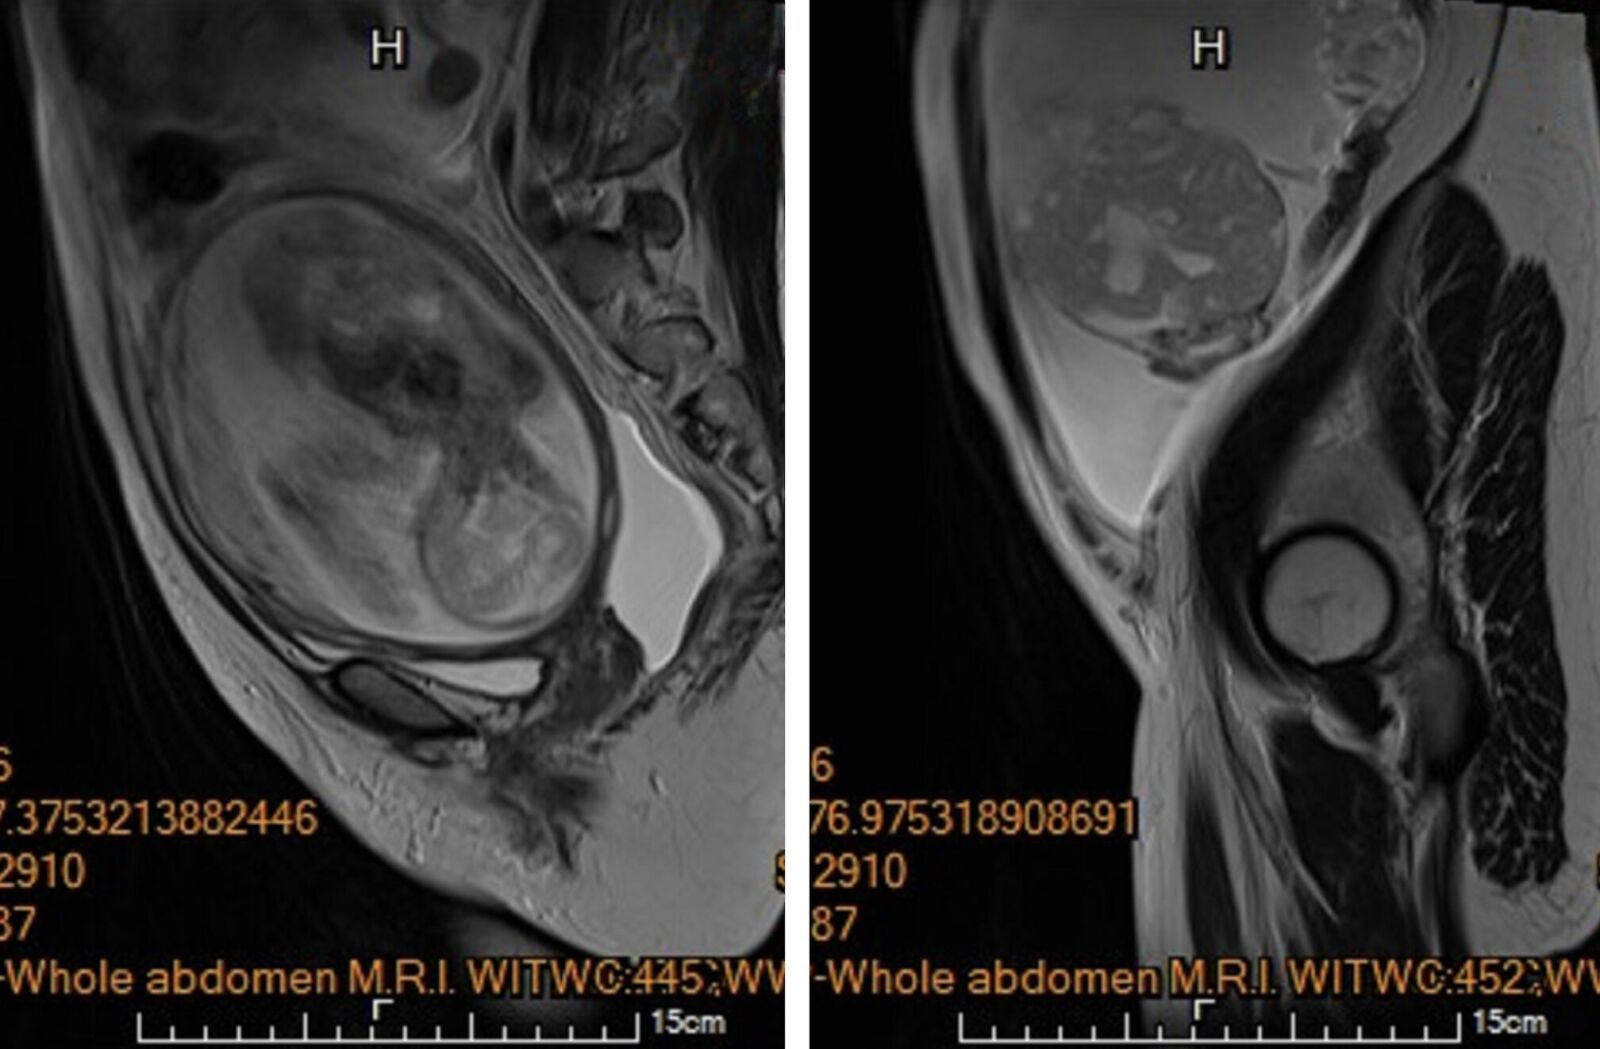

懷孕5個月,卻發現跟孩子一起長大的還有腫瘤!今年30歲、懷第一胎的李小姐就面臨這樣的危急狀況,產檢意外發現腹腔內積滿大量腹水,左側下腹部還驚見一個15公分大小、邊界模糊、結構複雜的卵巢腫瘤,惡性風險極高,可能得一次失去子宮跟胎兒,一度讓她萬念俱灰,所幸馬偕醫院醫療團隊儘速安排切除腫瘤,盡最大努力持續讓腹中胎兒長大到足月,自然產下2808公克的健康女寶寶。

馬偕醫院高危險妊娠科資深主治醫師王亮凱表示,李小姐是在妊娠20週進行第四次例行性產檢時,腹中胎兒發育情況一切正常,卻意外發現腫瘤,且已經有明顯的進食與呼吸困難等疑似腸胃道問題,高度懷疑是懷孕中合併卵巢癌。

馬偕醫院婦癌科主任陳楨瑞表示,經召集跨團隊討論後,考量當時胎兒屬於極低體重兒,預估體重尚不滿500公克,一旦早產存活率太低,加上惡性腫瘤妊娠中手術的風險太高,在慎重評估風險後決定,儘速安排手術切除腫瘤,且不論腹腔內轉瘤蔓延的嚴重度為何,均保留子宮與可能未被侵犯的右側卵巢輸卵管,盡最大努力持續讓腹中胎兒能長大到足月,同時保存未來生育能力。

陳楨瑞說,李小姐手術前,血液檢查發現異常超高的抗穆勒氏荷爾蒙(AMH)指數>22.5,而正常育齡女性數值介於2至5,已經強烈懷疑為卵巢顆粒細胞癌,馬上採傳統開腹手術,在不造成腫瘤破裂的情況下,順利切除包含惡性腫瘤的左側卵巢輸卵管,並取部分大網膜組織進行病理檢驗,幸運的是,手術時於腹腔內並沒有發現腫瘤擴散或轉移跡象,子宮與右側卵巢輸卵順利保留,子宮內胎兒也未受到手術影響。

陳楨瑞指出,病理報告雖證實為卵巢癌,但是屬於低度惡性的「幼年型顆粒細胞瘤」,免於後續在懷孕期間接受化學治療。李小姐術後恢復極佳,先前因腹水引起的腹脹、呼吸困難等症狀也完全消退,孕程得以順利延續,在妊娠38週,自然產下2808公克的健康女寶寶,產後門診追蹤無腫瘤復發跡象,寶寶也十分健康。